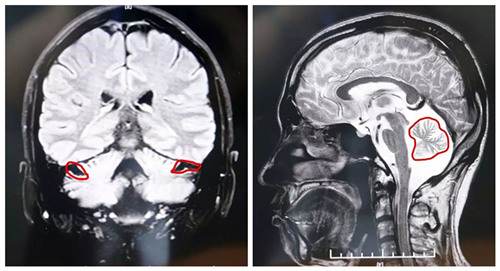

▲MRI顯示,患者小腦萎縮狀況明顯

可見小腦萎縮隨著病情的發(fā)展,患者在生活上、工作上會(huì)逐漸失去自主本能,中后期生活能力、機(jī)體控制能力會(huì)全面下降,直至臥床不起。若不及時(shí)進(jìn)行治療控制病情進(jìn)展,最終會(huì)直接威脅患者生命。